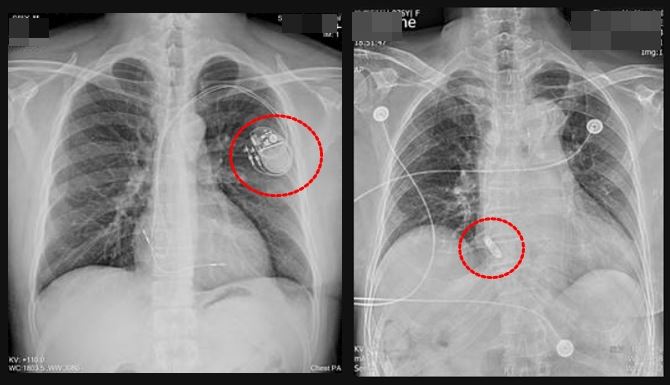

圖左為傳統心臟節律器,圖右為無導線心臟節律器,體積小如膠囊,可直接植入心腔 。(圖/雙和醫院提供)

圖左為傳統心臟節律器,圖右為無導線心臟節律器,體積小如膠囊,可直接植入心腔 。(圖/雙和醫院提供)76歲施姓婦人退休後常登山、運動、跳舞以維持健康。但最近感覺一動就會喘,走2、3階樓梯便須停下來換氣,而且不時會頭暈,就醫檢查後,發現她的心跳最慢時每分鐘僅跳12下,遠低於正常的60至100下範圍,確診「病竇症候群」,經植入右心房無導線心臟節律器後,這才恢復穩定心跳。

他說,竇房結病變初期症狀不明顯,隨病情惡化,可能逐漸出現胸口不適、心悸、頭暈、呼吸急促、疲勞及低血壓等情形,治療多以植入永久性心臟節律器,藉以改善心跳異常。值得注意的是,傳統心臟節律器包括電池和導線,導線一端埋在心肌,一端連結電池,此技術已成熟且多有健保給付。

不過林中行也指出,導線可能增加瓣膜損傷風險,也有掉落的可能,且因電池需埋於胸前皮下,會有胸前肌肉、皮膚的感染風險,病人也難進行大幅揮臂動作。如高爾夫球、網球或需頻繁使用肩關節與胸肌的球類運動,或是鍛鍊上肢的重量訓練也可能受限,且須避免將手機放置於患側胸前口袋,以免影響節律器運作。

他說,考量患者平日熱愛運動,經醫療團隊評估,決定採心導管微創方式植入右心房無導線心臟節律器,裝置體積如膠囊,可直接置放於右心房或右心室內,無需導線及胸前囊袋,可降低感染及氣胸等併發症,外觀也不易察覺,手術約1小時完成,術後3天即出院,回診狀況良好。呼籲年長者若出現稍微活動就喘、頭暈、心悸或容易疲勞等情形,常誤以為只是老化或體力下降,應及早就醫檢查。